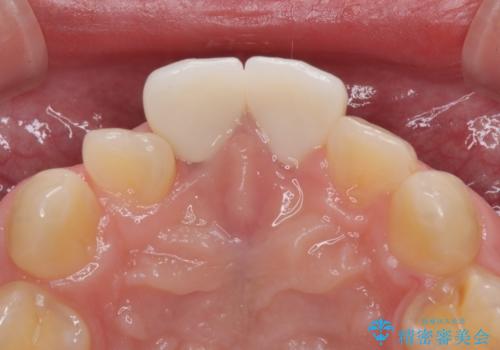

噛み合わせを改善するための矯正治療をご提案しましたが、患者様のご希望により矯正治療と根管治療の再治療は行わず、ファイバーコア(土台)+オールセラミッククラウンによる補綴治療を選択しました。

審美性と強度を両立させるため、透明感のあるオールセラミッククラウンを採用し、周囲の天然歯に自然に調和するよう色調・形態を調整しました。